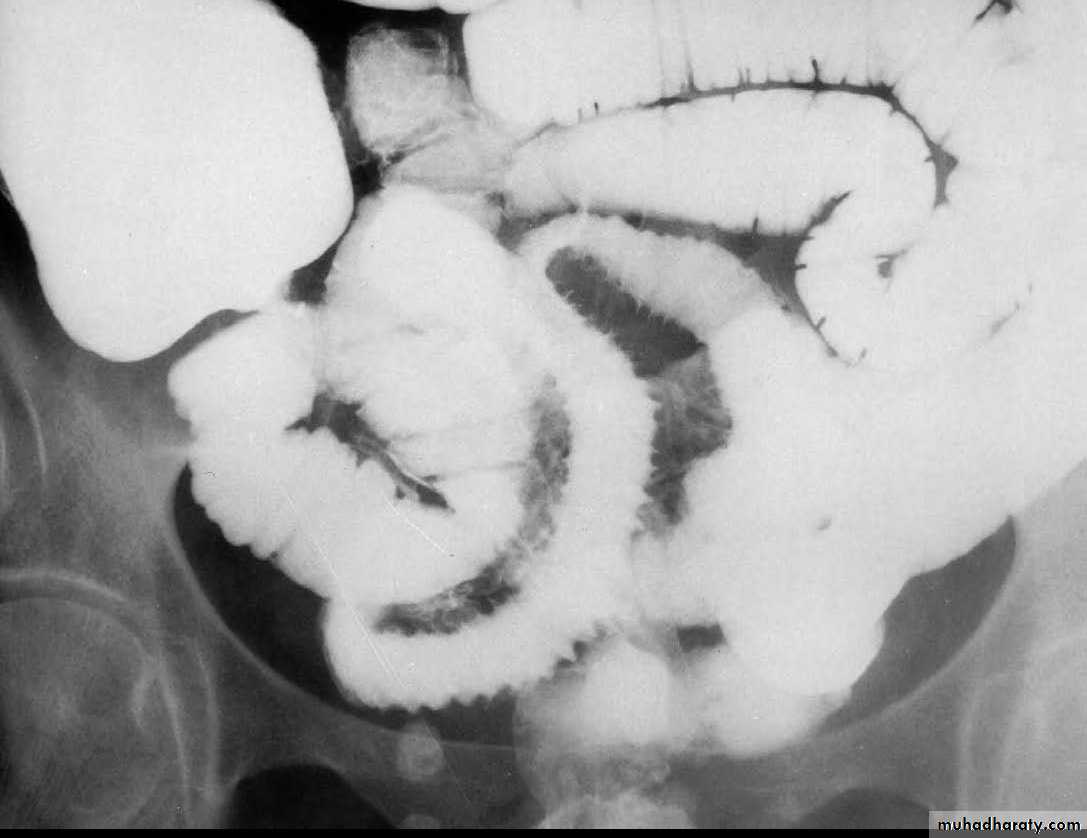

An intraluminal polypoid mass is present within the smallbowel. Small bowel

A long segment of terminal ileum is involved with multiple submucosal, polypoid filling defects. The lumen is increased in diameter